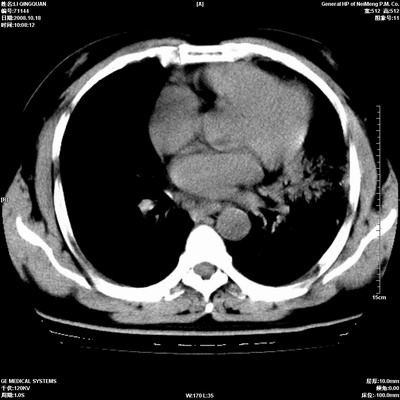

以下是引用duguo在2008-10-19 13:59:00的发言:[br]左肺上叶支气管狭窄,首先考虑中心型肺癌伴阻塞性肺炎\\肺不张.

以下是引用ybing在2008-10-19 12:58:00的发言:[br]左肺上叶阻塞性炎症-建议支气管镜进一步检查除外中央型肺癌

以下是引用随光逐影在2008-10-19 14:31:00的发言:[br]考虑左肺中央型肺癌并左肺上叶阻塞性肺炎,肺不张。